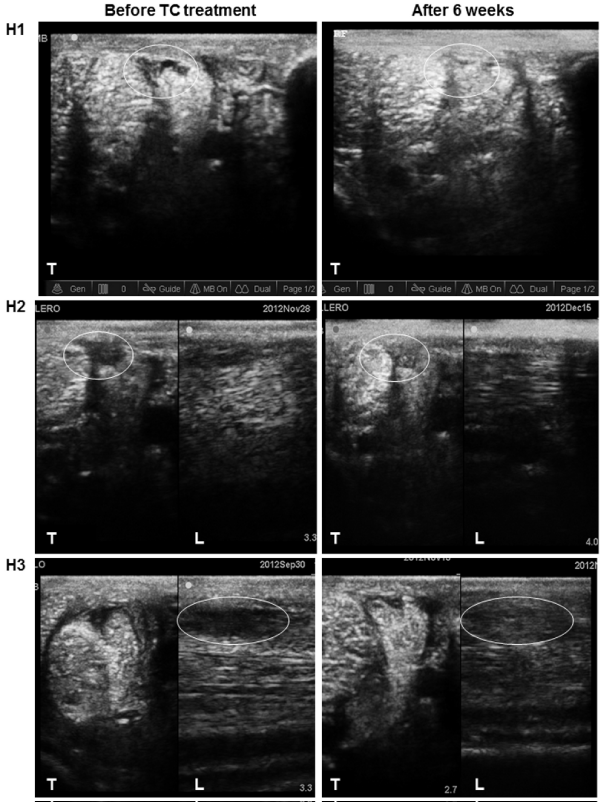

| Figure 6: Transversal (T) and longitudinal (L) ultrasound images of a lesion (white circle) in accessory ligament of the deep digital flexor tendon (ALDDFT) in 3 horses (H) before (left column) and 6 weeks after (right column) treatment with tenogenic induced allogenic mesenchymal stem cells (Tendo-Cell® =TC). At approximately 6 weeks after the treatment, a score 4 was given to all the treated ALDDFTs, because although the fiber orientation was completed, there were still some small hypo-echoic zones. |